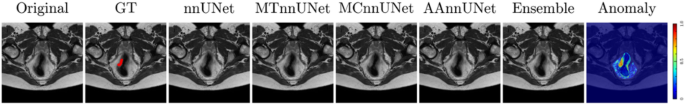

MTnnUNet, MCnnUNet and AAnnUNet (Fully-Supervision)

From Table 4, S6 and Fig. 4a, MTnnUNet and AAnnUNet significantly outperformed both nnUNet and MCnnUNet. Even though MCnnUNet showed the best results in the internal validation (Table S7), it exhibited the lowest aDSC and aHD in the external test. This may be due to MCnnUNet’s reliance on accurate anatomical inputs. It was trained with ground truth anatomical masks but used AI-generated masks (rectum and mesorectum) during inference, introducing inconsistencies that likely contributed to the performance drop on the external test. Unlike MCnnUNet, MTnnUNet uses anatomical knowledge only during training. Although AAnnUNet—fusing anomaly maps that highlight tumoral regions—also relied on the quality of rectum and mesorectum masks, it slightly outperformed MTnnUNet in terms of aDSC. Unlike MCnnUNet, which directly incorporated anatomical masks as input channels, AAnnUNet utilized anomaly maps derived from healthy distributions. We also introduced a union ensemble combining MTnnUNet and AAnnUNet, which improved aDSC by 3%. However, it did not reduce HD. Figure 5 shows that AAnnUNet effectively segmented both small and large tumors, demonstrating the benefit of anomaly fusion. Furthermore, the Grad-CAM saliency map in Fig. S2 indicates that AAnnUNet more effectively captures tumoral features. However, its performance declined when anomaly maps were suboptimal, as seen in the last row. In some cases, all models failed to detect the tumor, though high anomaly map intensities—illustrated in Fig. 6—still indicated potential abnormalities.

The visualization of the segmentation performance of nnUNet, MTnnUNet, MCnnUNet, AAnnUNet, and Ensemble using T2WI, supervised setting. Each row is a different sample from the external test set. The columns from left to right are original T2WI, ground truth, tumor prediction masks from nnUNet, MTnnUNet, MCnnUNet, AAnnUNet, and Ensemble. Colorbar: Shows pixel-wise reconstruction error; higher values indicate greater differences and potential anomalies.

In both fully- and mixed-supervision, MTnnUNet outperformed the baseline nnUNet. MCnnUNet showed improvement only in mixed-supervision. Notably, incorporating anomaly maps enhanced tumor localization accuracy across both settings. As illustrated in the first row of Fig. S3, while nnUNet misclassified part of the bladder as tumor due to similar intensities, MTnnUNet, MCnnUNet, and AAnnUNet—fusing anatomical masks or anomaly maps—correctly identified the tumor regions.